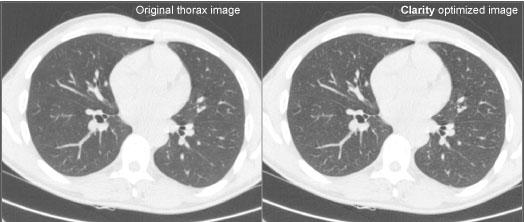

A comparison of the original and Clarity-enhanced CT image from Philips Brilliance 64, showing a 3 mm contrast-enhanced thorax slice at 133 mAs, 120 KVP.

The facility used the Clarity CT Solution software made by Saphenia. The system was connected to the facility’s Philips Brilliance 64 CT and Siemens PACS. Data acquired from the scanner were reconstructed on the scanner before post-processing on the Clarity server. From there DICOM images were transferred to the PACS and Philips workstation. In addition, unprocessed raw data was transferred to the workstation for comparison and secondary reconstruction purposes.

The mean radiation dose in the 35 low-dose patients was 2.41 mSv. The mean dose in the 10 full-dose patients was 5.29 mSv, while the national average dose in Norway is 10 mSv (1). Use of the software contributed to a 53.3 percent and 74.1 percent reduction respectively. If only the last 16 patients were considered, the average dose was 1.55 mSv. This translates into an 84 percent reduction from average dose for Norway and a 70 percent reduction from Unilabs’ average full-dose scans. Image quality and diagnostic value was considered good or very good by all reporting radiologists.